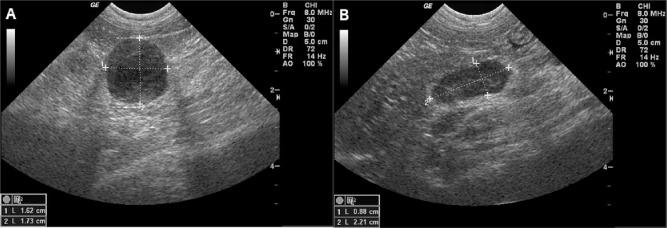

A 10-year-old, 5.1 kg (11.2 lb), male castrated cat was presented with signs of lethargy and decreased appetite at home after being previously healthy. Serum biochemical analysis identified normokalemia (5.1 mmol/l; reference interval [RI] 3.4-5.6 mmol/l) and severe hyponatremia (123 mmol/l; RI 145-158 mmol/l), with an Na/K ratio of 24 (RI 32-41). Baseline serum cortisol was low to normal, but serum aldosterone was markedly decreased with a pre-adrenocorticotropic hormone stimulation concentration of 13 pmol/l (RI 194-388 pmol/l) and post-adrenocorticotropic hormone stimulation concentration of 21 pmol/l (RI 277-721 pmol/l). Hematologic and biochemical analyses were otherwise unremarkable. Abdominal ultrasound revealed bilaterally enlarged adrenal glands with no other abnormalities noted; thoracic radiographs also did not identify any signs of metastasis. Fine-needle aspiration was strongly suggestive of lymphoma of the adrenal glands, and PCR for antigen receptor rearrangement was positive for B-cell clonal expansion; based on these findings, a diagnosis of primary adrenal B-cell lymphoma was made. Stable disease was achieved for a short period of time following vincristine, cyclophosphamide, prednisolone and fludrocortisone therapy, followed by progressive adrenal enlargement and electrolyte derangements that responded to neither doxorubicin nor adjustments in fludrocortisone dosage. Ultrasonographic metastasis was not identified at any time, and other organ derangements were not noted on hematologic or biochemical analyses. The cat was euthanized 55 days after initial presentation.

一只10岁、体重5.1千克(11.2磅)的去势雄性猫,此前健康,在家中出现嗜睡和食欲减退的症状。血清生化分析显示血钾正常(5.1毫摩尔/升;参考区间[RI] 3.4 - 5.6毫摩尔/升),严重低钠血症(123毫摩尔/升;RI 145 - 158毫摩尔/升),钠/钾比值为24(RI 32 - 41)。基础血清皮质醇水平低至正常,但血清醛固酮显著降低,促肾上腺皮质激素刺激前浓度为13皮摩尔/升(RI 194 - 388皮摩尔/升),促肾上腺皮质激素刺激后浓度为21皮摩尔/升(RI 277 - 721皮摩尔/升)。血液学和生化分析其他方面无异常。腹部超声显示双侧肾上腺肿大,未发现其他异常;胸部X光片也未发现转移迹象。细针穿刺强烈提示肾上腺淋巴瘤,抗原受体重排的聚合酶链反应显示B细胞克隆性扩增呈阳性;基于这些发现,诊断为原发性肾上腺B细胞淋巴瘤。长春新碱、环磷酰胺、泼尼松龙和氟氢可的松治疗后短期内病情稳定,随后肾上腺逐渐增大,电解质紊乱加重,多柔比星治疗及氟氢可的松剂量调整均无效。在任何时候均未发现超声检查提示的转移,血液学或生化分析也未发现其他器官紊乱。该猫在初次就诊后55天实施安乐死。